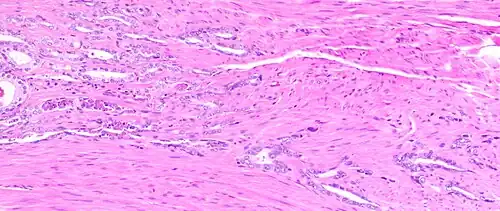

-

Atrophy is a differential diagnosis to prostate cancer. This example shows gradually increasing simple atrophy from left to right, H&E stain. Crowding and angulation may mimic that of adenocarcinoma, but there is nuclear basophilia rather than atypia, and occasional basal cells can still be seen.

Atrophy is a differential diagnosis to prostate cancer. This example shows gradually increasing simple atrophy from left to right, H&E stain. Crowding and angulation may mimic that of adenocarcinoma, but there is nuclear basophilia rather than atypia, and occasional basal cells can still be seen. -